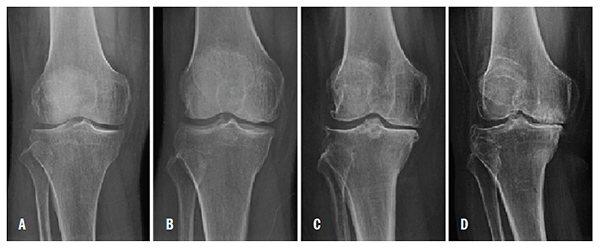

At present, the diagnosis of OA of the knee primarily depends on clinical symptoms and radiographic findings. Conventional radiography is still being used as a standard imaging technique for the evaluation of known or suspected OA in clinical practice and research. (Figure 1)

Kellgren-Lawrence radiographic grading criteria is generally the assessment tool used in the evaluation of OA in the knee. This is a problem because most individuals are clinically asymptomatic in the early stages of OA, and often pathological degradation of the articular cartilage already exists before the symptoms arise.